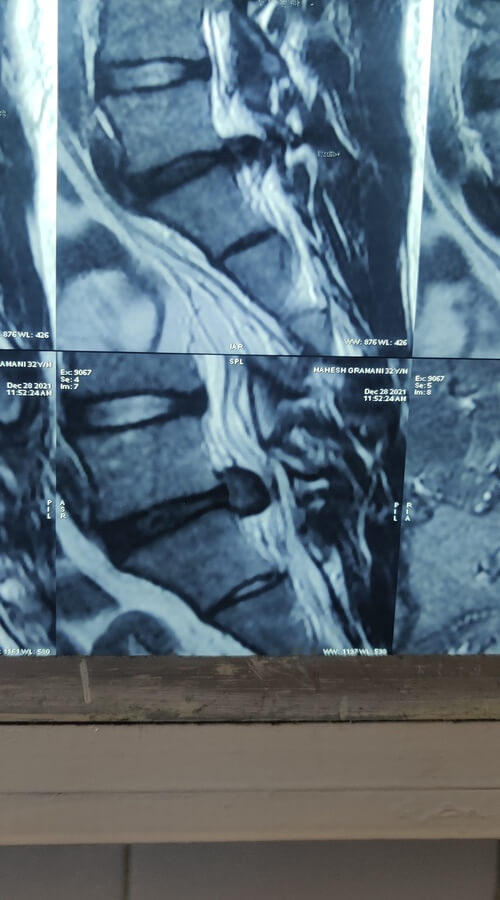

Spine Specialist

Endoscopic Spine Surgeon

- Successfully Done More Than 5000+ Spine Surgeries

- Successfully Done More Than 1000+ Endoscopic Spine Surgery